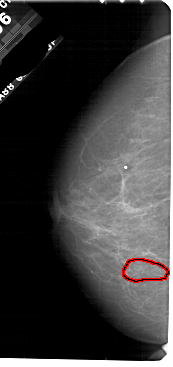

A_1839_1.LEFT_MLO

LEFT_MLO LINES 5491 PIXELS_PER_LINE 2851 BITS_PER_PIXEL 12 RESOLUTION 43.5 OVERLAY

FILE: A_1839_1.LEFT_MLO.OVERLAY

TOTAL_ABNORMALITIES 1

ABNORMALITY 1

LESION_TYPE CALCIFICATION TYPE PLEOMORPHIC DISTRIBUTION CLUSTERED

ASSESSMENT 4

SUBTLETY 3

PATHOLOGY BENIGN

TOTAL_OUTLINES 1

BOUNDARY